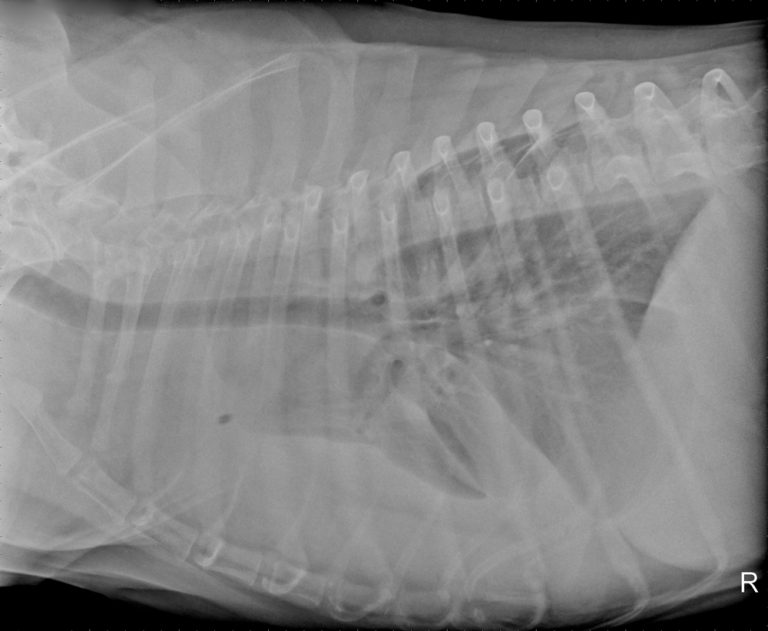

Diagnosing Canine Abdominal Organ Torsions

From glencoeanimalhospital.com

ABDOMINAL RADIOGRAPHY Canine Glencoe Animal Hospital What Can Cause Fluid In Dog's Stomach Knowing the type of fluid in your dog’s abdomen can help narrow down the causes. When fluid builds up in the abdomen, your dog's stomach will be visibly distended. What causes ascites in dogs? Several health conditions can cause ascites,. Ascites in dogs is an abnormal buildup of abdominal fluid that occurs as a result of an underlying disease. Only. What Can Cause Fluid In Dog's Stomach.

From todaysveterinarypractice.com

Diagnosing Canine Abdominal Organ Torsions What Can Cause Fluid In Dog's Stomach What causes ascites in dogs? Ascites in dogs is an abnormal buildup of abdominal fluid that occurs as a result of an underlying disease. Several health conditions can cause ascites,. Knowing the type of fluid in your dog’s abdomen can help narrow down the causes. One study in 70 dogs showed that hemorrhaging was the most common cause of ascites,.. What Can Cause Fluid In Dog's Stomach.